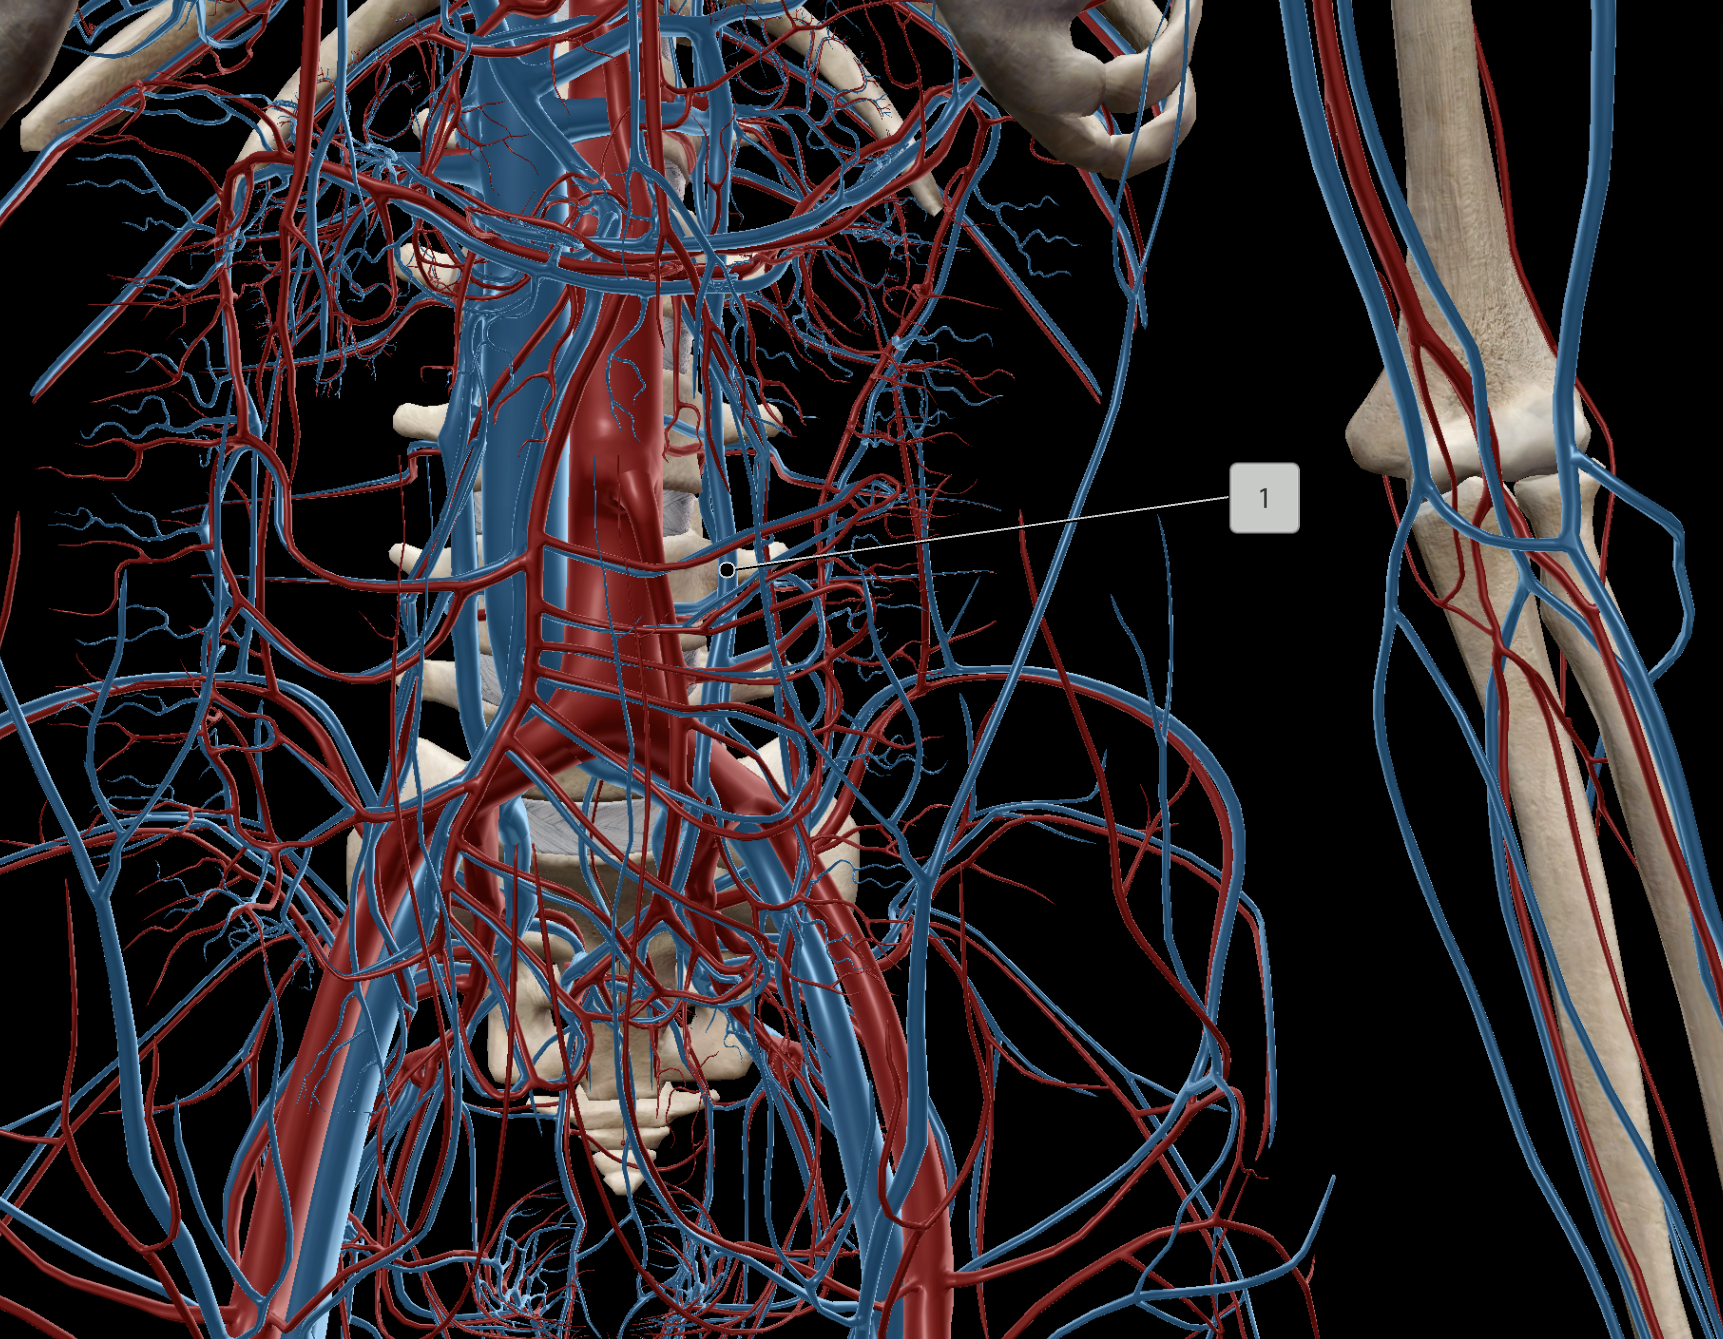

Abdominal Aorta

Inferior Vena Cava

Common Iliac Artery

Internal Iliac Artery

External Iliac Artery

Inferior Mesenteric Artery

Superior Mesenteric Artery

Common Iliac Vein

External Iliac Vein

Internal Iliac Vein

Superior Mesenteric Vein

Inferior Mesenteric Vein